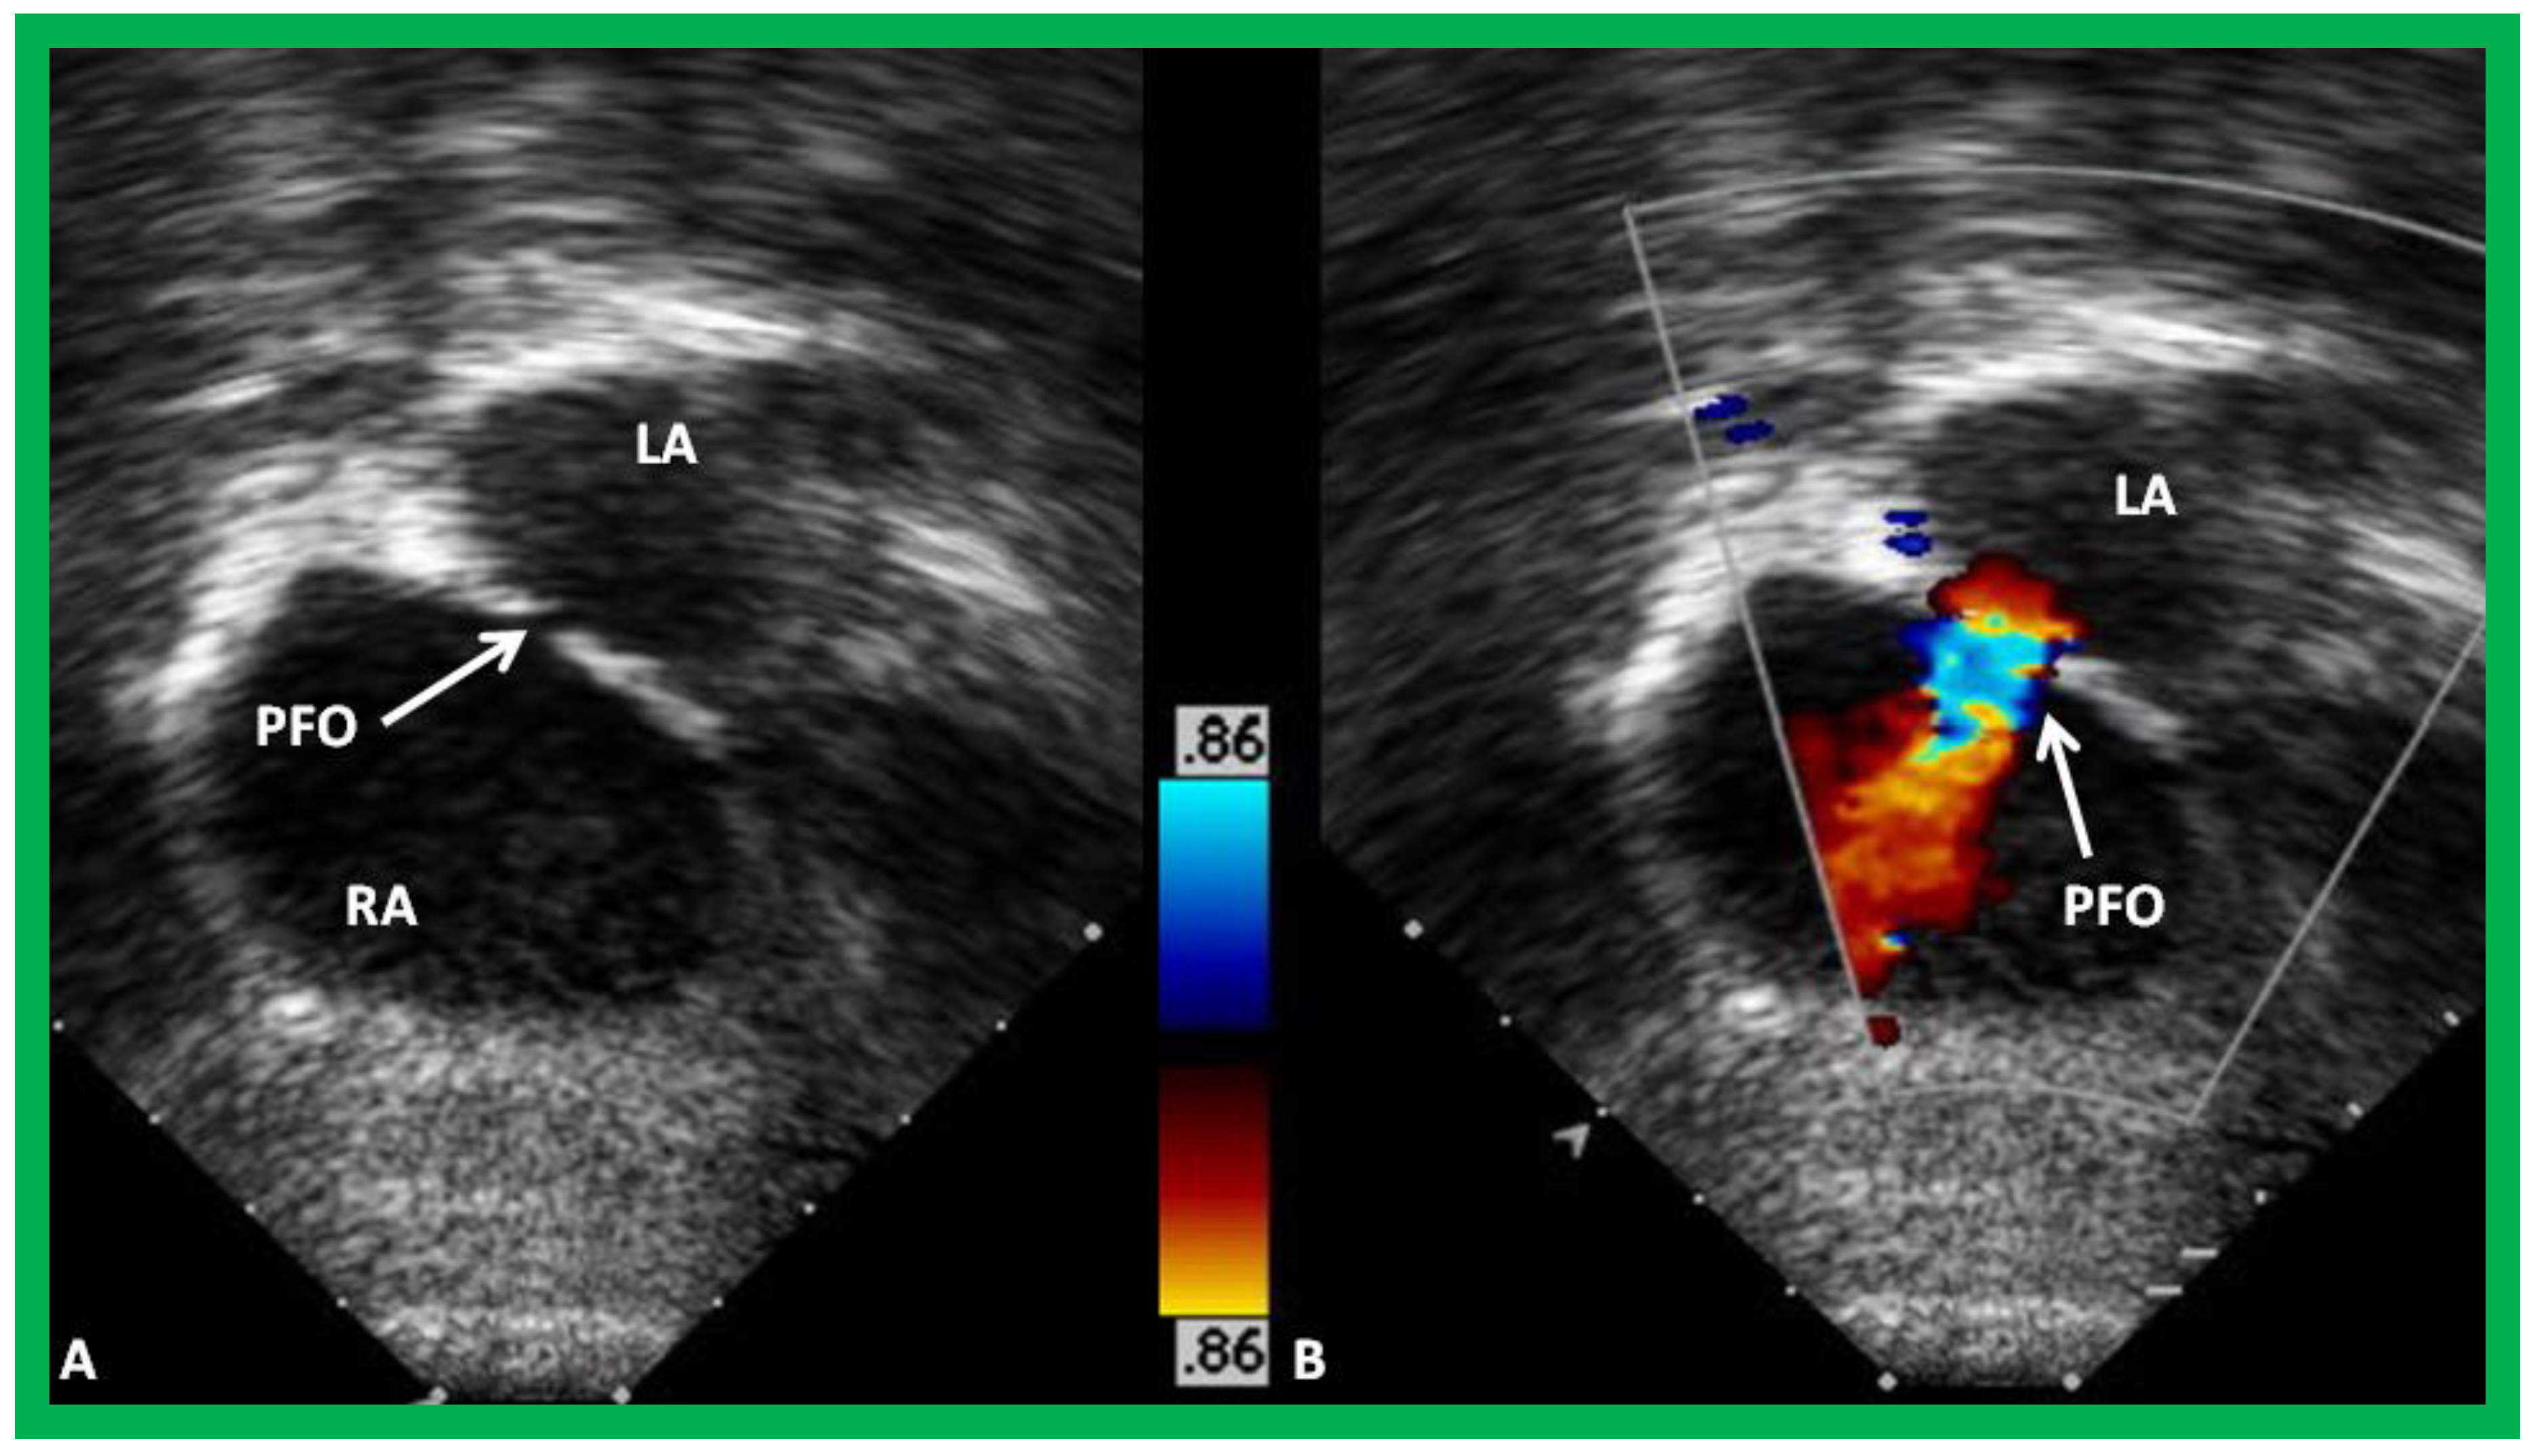

8. Echocardiogram